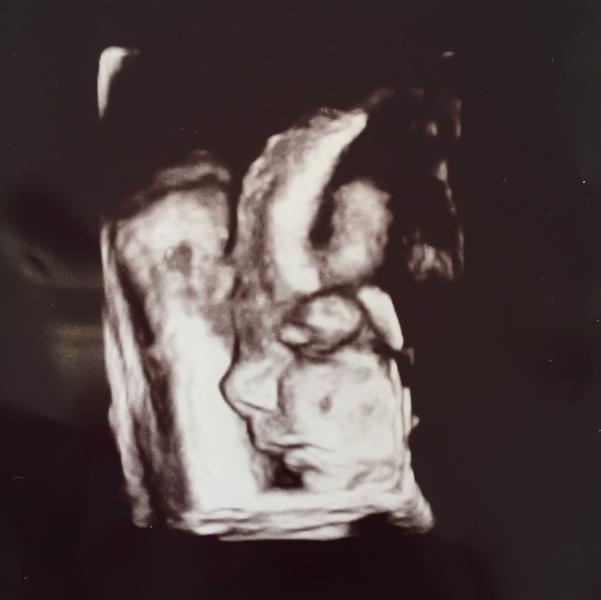

Девочки😊😎Уже вроде более менее пришла в себя,поэтому напишу свою #историяродов 10 мая мой гинеколог отправила меня в роддом со словами-Ты рожаешь🙄В итоге роддом оставил меня в своих стенах,обещав,что если роды не наступят через неделю,то будем пить волшебную таблеточку 💊так как уже срок и мой мальчик крупненький👍За неделю никаких изменений не было,сын любил мой животик😭поэтому 16 мая и первая таблетка...я была так счастлива😌далее немного начал болеть живот ночью,как при месячных,спасала ношпа...следующий денб и еще одна таблетка...и тут то всё и началось😫😫😫схватки по нарастающей,это было больно...очень...но по сравнению с тем,что было впереди....😔Очень не хочу никого пугать,но скажу одно,рожать в следующий раз я буду только с эпидуралкой!так как такого просто не выдержу и врятли забуду😭Итак...в 17 часов 17 мая после сильно сократившегося интервала схваток меня посмотрели на кресли и отправили в род отделение🚺это было уже кошмар...клизма,схватки,я тогда еще стонала...далее положили на кушетку,ктг,обезболивающее,которое как я поняла дает поспать 2 часа,но я не поняла вообще,что я спала...всё в бреду...я орала,дышала,просила помощи,говорила,что заплачу любые деньги только помогите😅звала всех,кого возможно,бога ,маму,мужа и любого кто бы мне помог😅(сейчас конечно это смешно)....Врачи меня ругали,обьясняли,и мне это очень понравилось👍вообщем наконец дождалась слов-Пошли на кресло,будем рожать😵я была счастлива,оставалось немного....за 4 или 5 потуг(точно не помню)родила я нашего мальчика сладкого,4160 кг и 58 см....Сильно порвалась,также резали,4 шва😞вообщем я так счастлива,так его люблю🤗🤗🤗❤️❤️❤️❤️это чудо ❤️❤️❤️Фото-это мой сыночек на узи💛💛💛💛💛💛💛